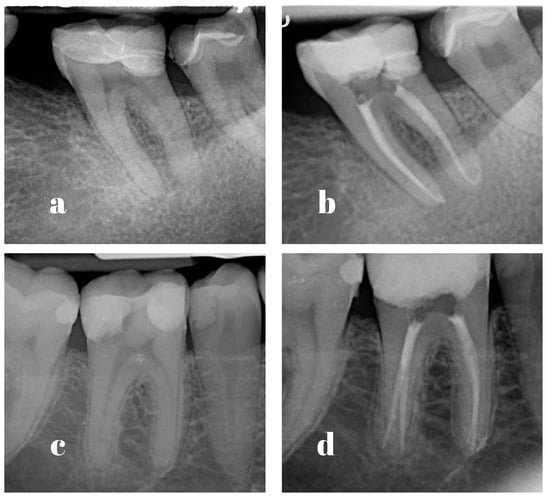

Figure 2.

Examples of cases performed by PGSs ((a) pre-operative radiograph; (b) post-operative radiograph) and ESs ((c) pre-operative radiograph; (d) post-operative radiograph).